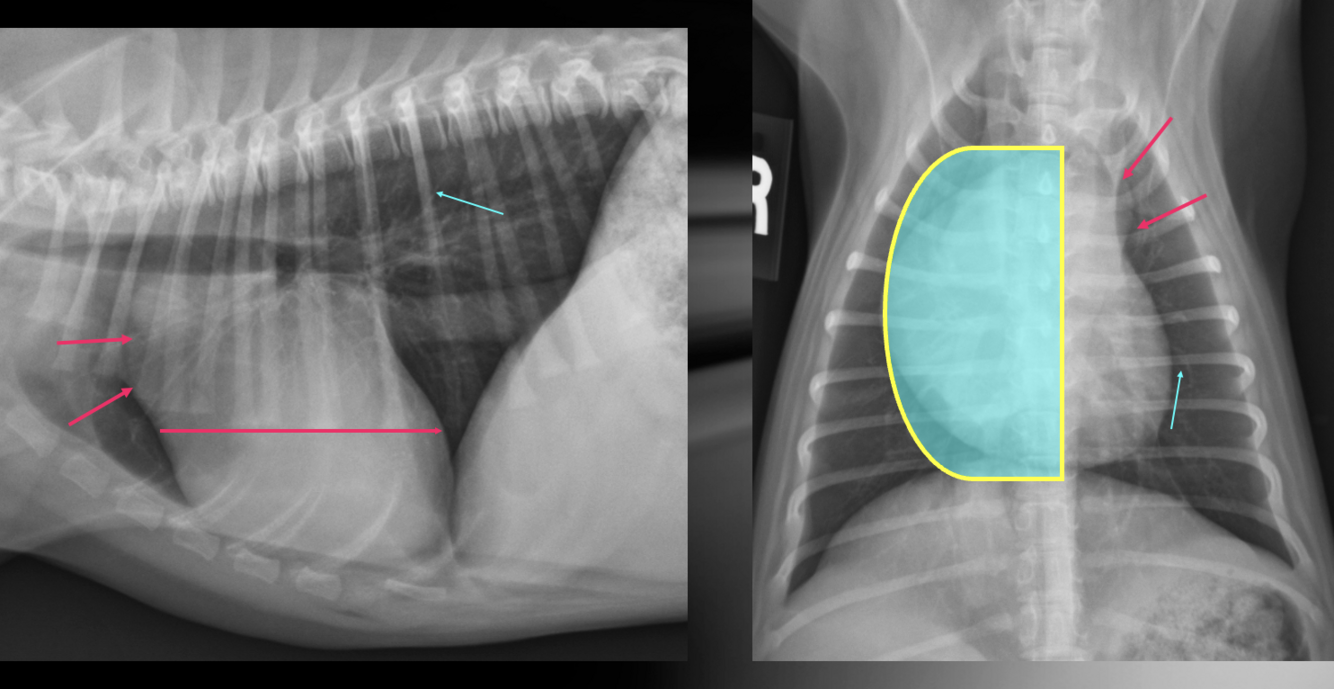

What is shown in these images?

A

pulmonic stenosis

-right heart enlargement

-main pulmonary artery segment enlargement

-possible right heart failure

What are the radiographic findings of pulmonic stenosis?

-right heart enlargement (RVE +/- RAE) due to pressure overload

-normal to small pulmonary vessels